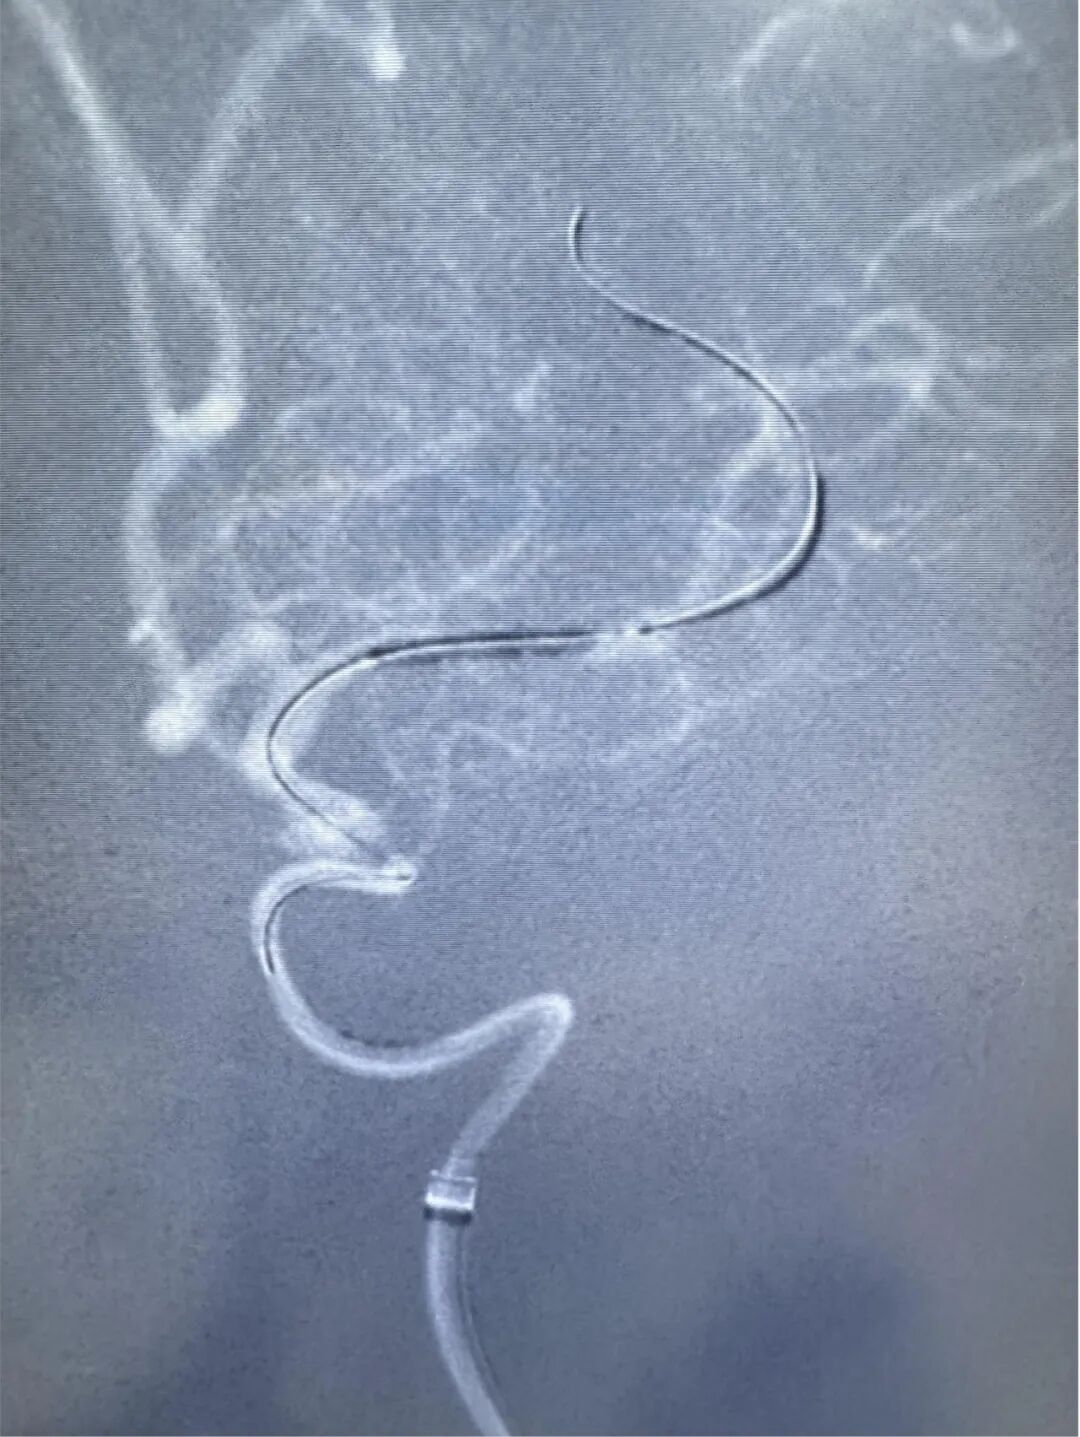

颅内血管纤细且脆弱,正常血管也只有2.25毫米,在重度狭窄的颅内血管内放置支架是一项严峻挑战。郭宗培、陈历、熊建医生、聂毅医生团队,身披重达15斤的铅衣,操控堪比头发丝样的导丝,球囊适度扩张狭窄血管,精准释放颅内药物涂层支架,使血管狭窄解除,远端血管再次丰富充盈,为减少以后发生脑梗塞的可能性打下坚实基础。整个过程需要团队的团结紧密协作,这场手术考验的是医生的整体医疗素质。